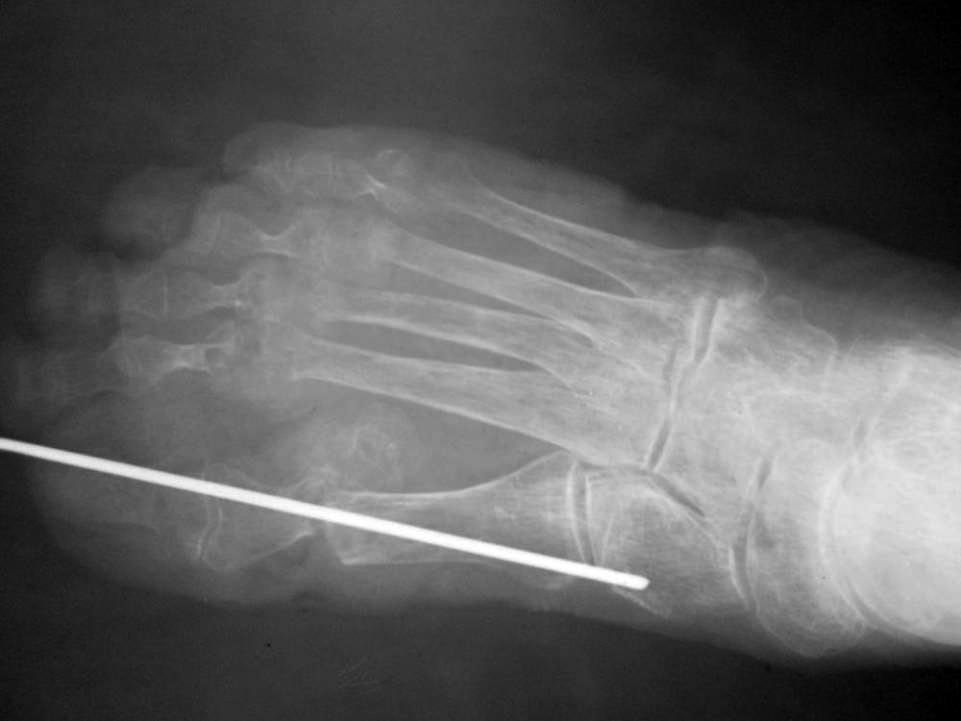

Пациентке выполнен артродез 1-ого плюснефалангового сустава, резекции

говок 2-3 плюсневых костей, субкапитальная остеотомия 4 плюсневой кости,

тенотомиии разгибаталей 2-5 п. стопы. Раны зажили первичным натяжением.